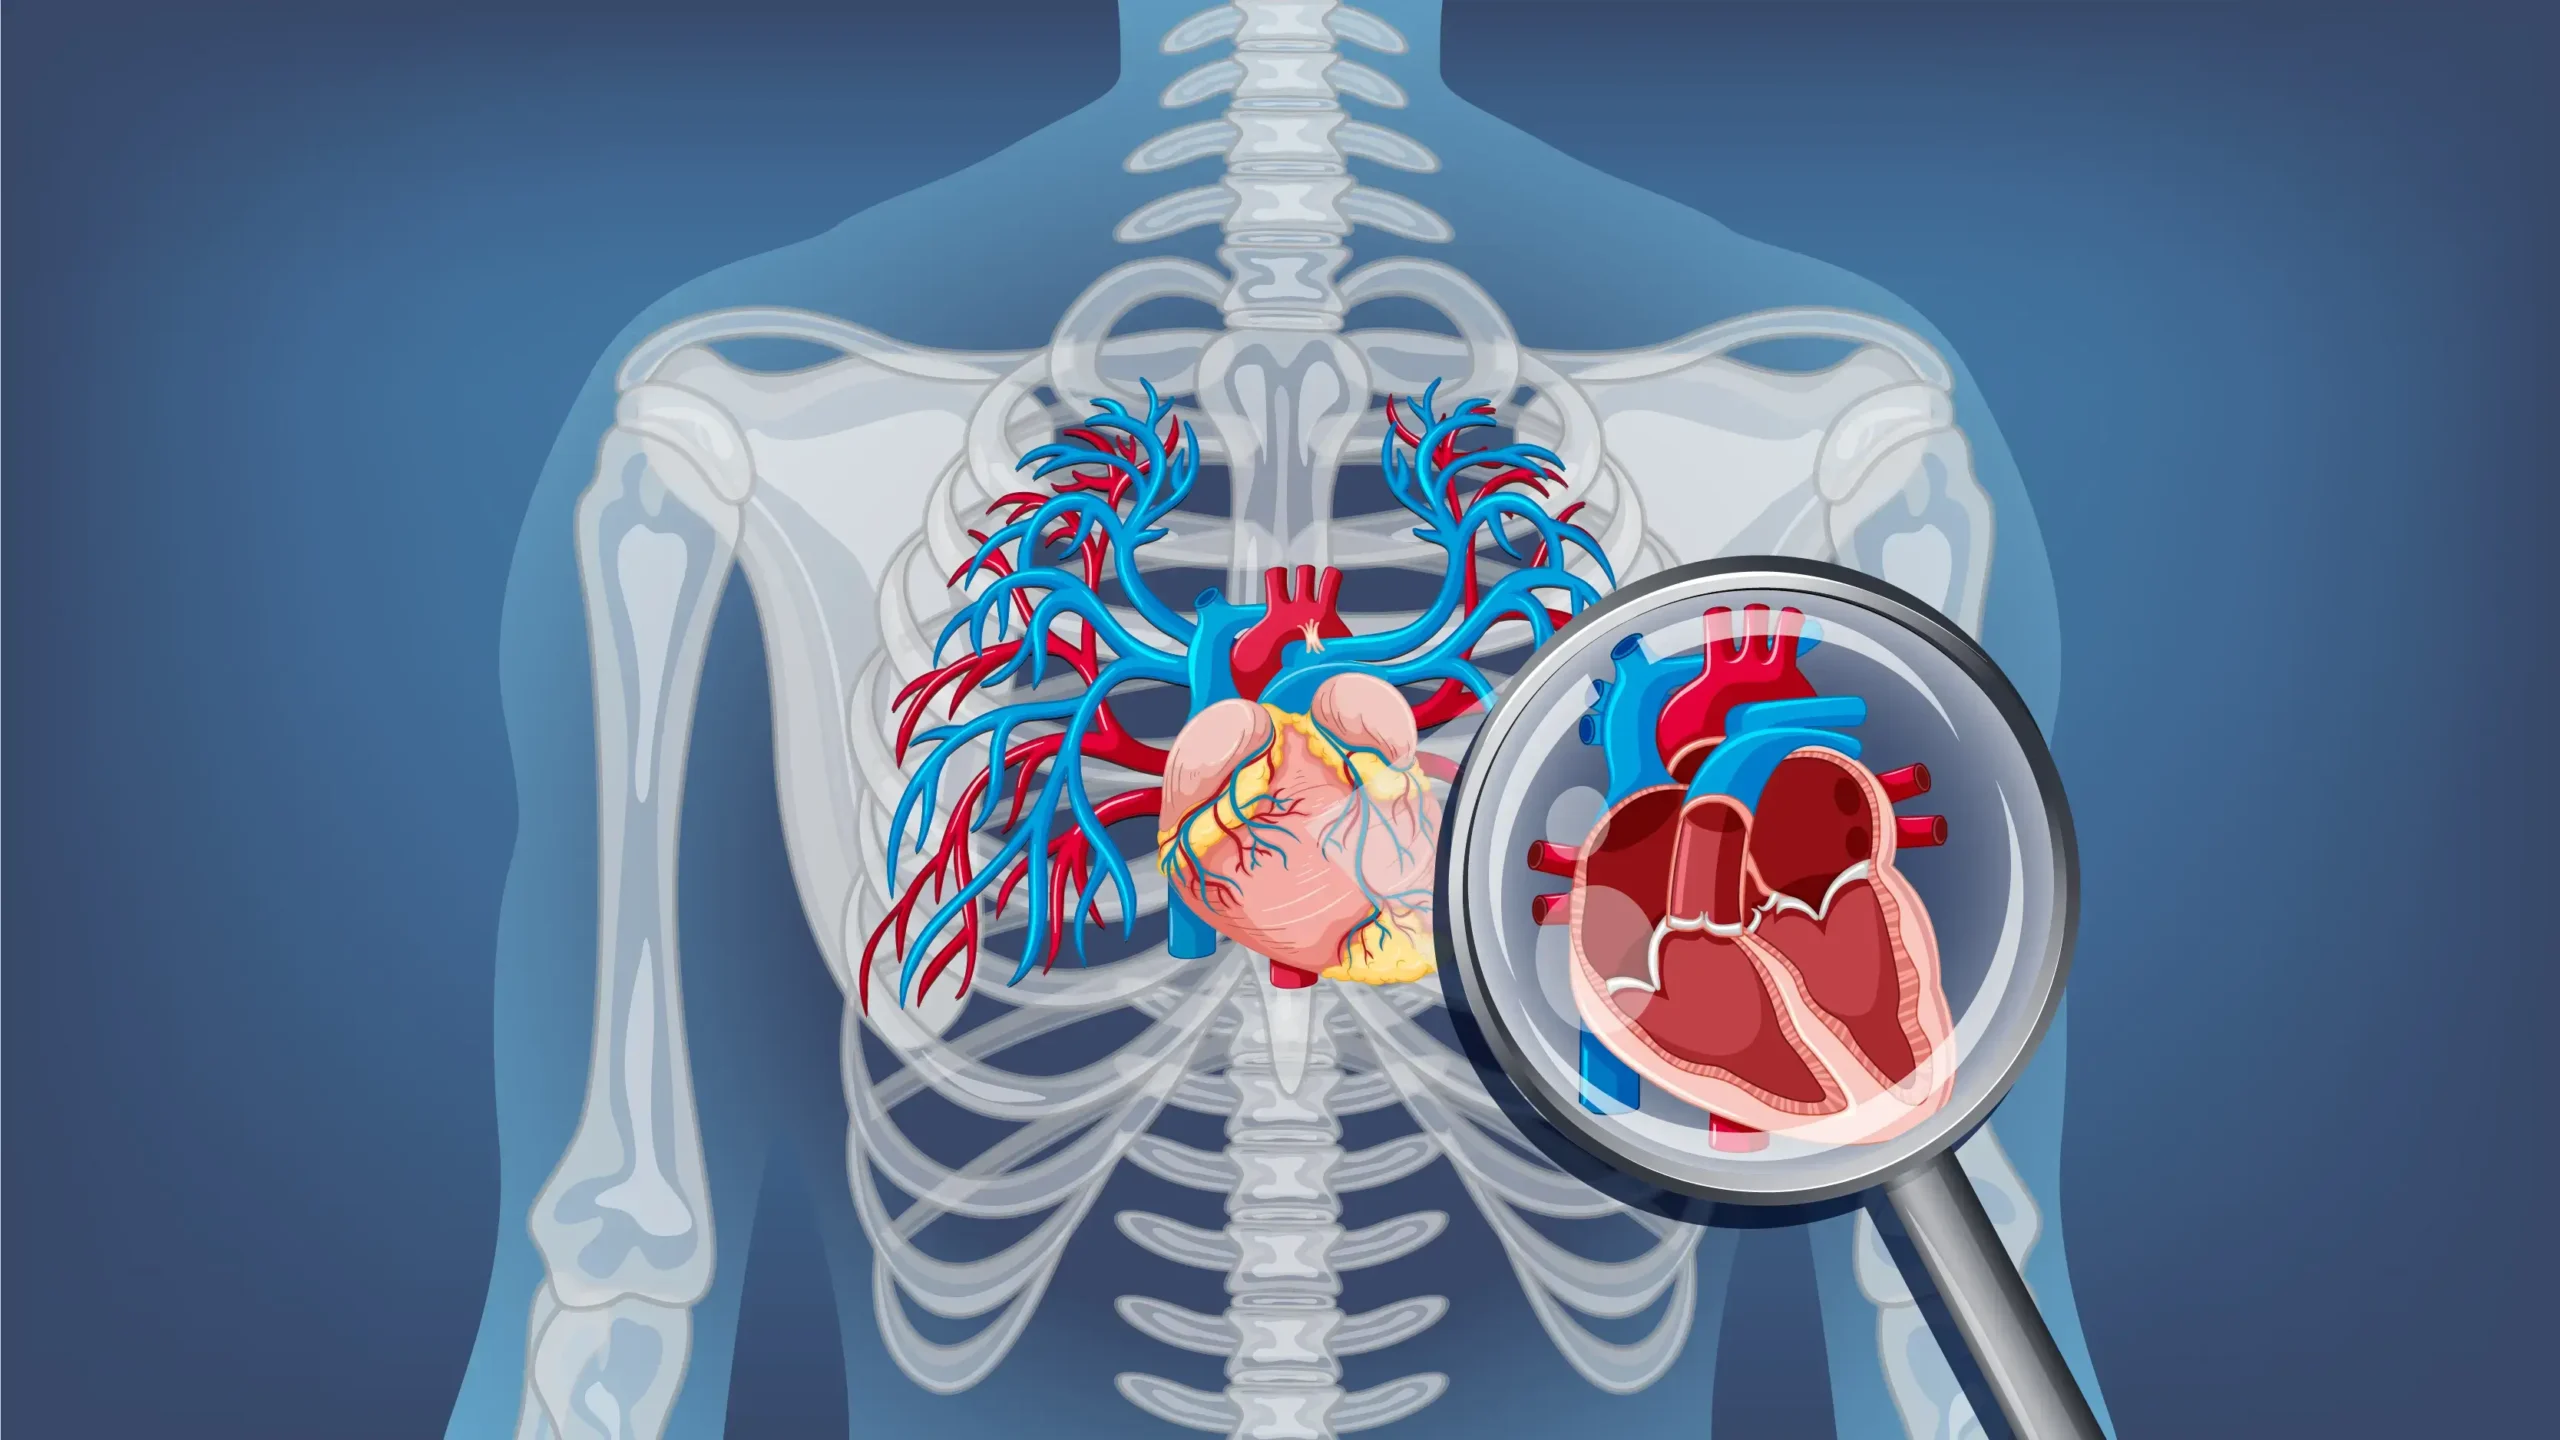

A CT coronary angiogram (CTCA) is a heart imaging test that helps me see if plaques have narrowed your coronary arteries, the blood vessels that supply your heart. Plaque is made of substances such as fat, cholesterol, and calcium that can build up along the walls of your arteries over time. This build up can reduce, or in some cases block, blood flow to your heart.